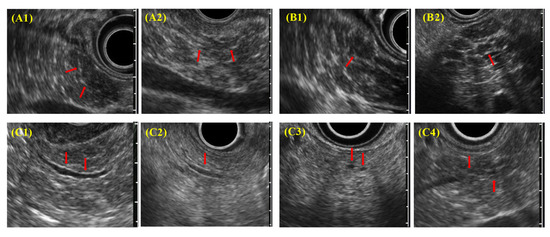

EUS diagnostic findings (Figure 3) include (A) hyperechoic foci with nonshadowing or stranding, (B) lobularity (nonhoneycombing or honeycombing type), (C) hyperechoic MPD margins, and (D) dilated side branches. ECP is diagnosed by imaging when two or more findings, including (A) or (B) or both, are observed. In addition, irregular dilatation in three or more branched pancreatic ducts, as seen on ERCP or magnetic resonance cholangiopancreatography, also served as imaging findings for ECP.

Figure 3. Each EUS finding in DCECP2019; (A1,A2) hyperechoic foci; nonshadowing/stranding; (B1,B2) lobularity (nonhoneycombing/honeycombing type); (C1,C2) hyperechoic MPD margins; (C3,C4) dilated side branches.